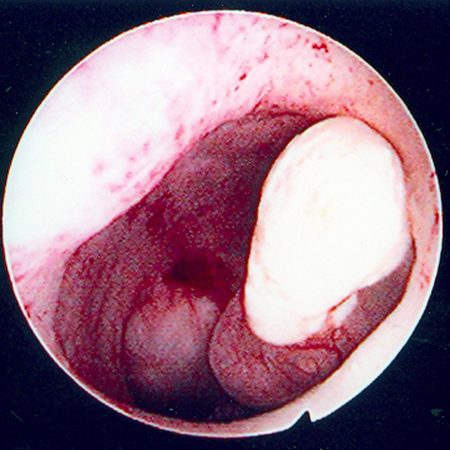

Hysteroscopic examination of the uterine cavity demonstrates the presence of two contiguous submucous uterine fibroids in this patient with persistent heavy menstrual bleeding

From the personal collection of Dr M.F. Mitwally and Dr R.J. Fischer; used with permission